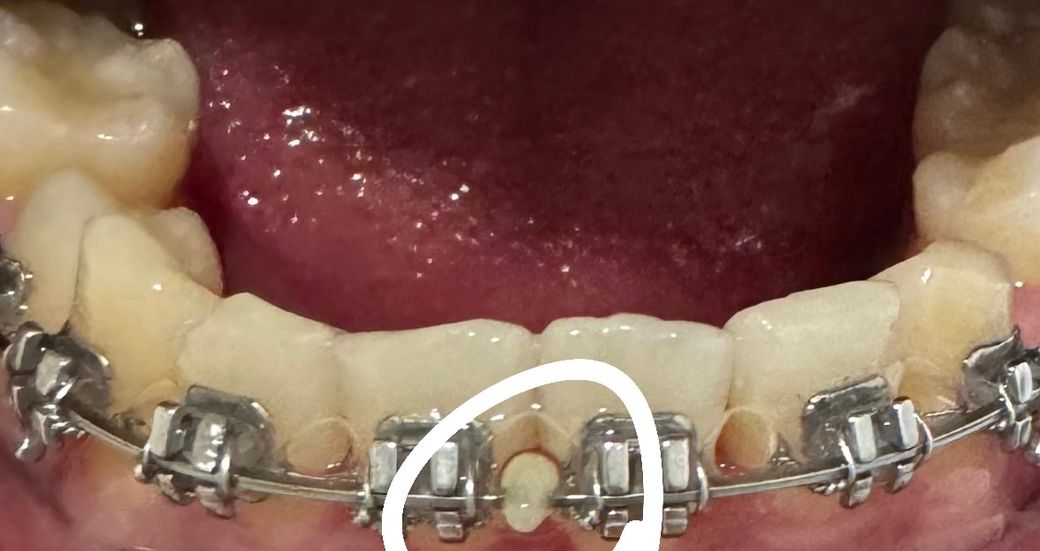

처음에 음식물인줄 알고 봤는데 음식물이 아니라 딱딱한 무언가가 박혀있습니다 혹시 뭔지 알 수 있을까요?? 집에 와서 보니까 이렇게 되있어서 치과에서 물어보지를 못했습니다

• 해당되는 부위는 교정을 할 때 철사가 이동하지 않도록 스탑을 준 것으로 보입니다.

또한 중심점을 확인하기 위한 것일 수도 있습니다. 자세한 확인을 위해서 교정치과에서 진료를 받아보는 것을 권유드립니다

• 중간 부분 철사를 의도적으로 고정해두기 위해 레진이라는 치과재료를 붙여둔 것 같습니다. 교정 치료와 상관이 있는지 해당 교정치과의사에게 물어보시기 바랍니다.